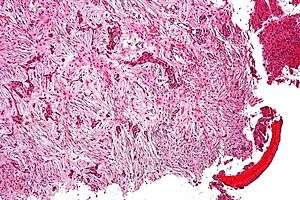

Micrograph of an adamantinoma showing the biphasic histomorphology. H&E stain.. | |

Histologically, islands of epithelial cells are found in a fibrous stroma. The tumor is typically well-demarcated, osteolytic and eccentric, with cystic zones resembling soap bubbles.[2]